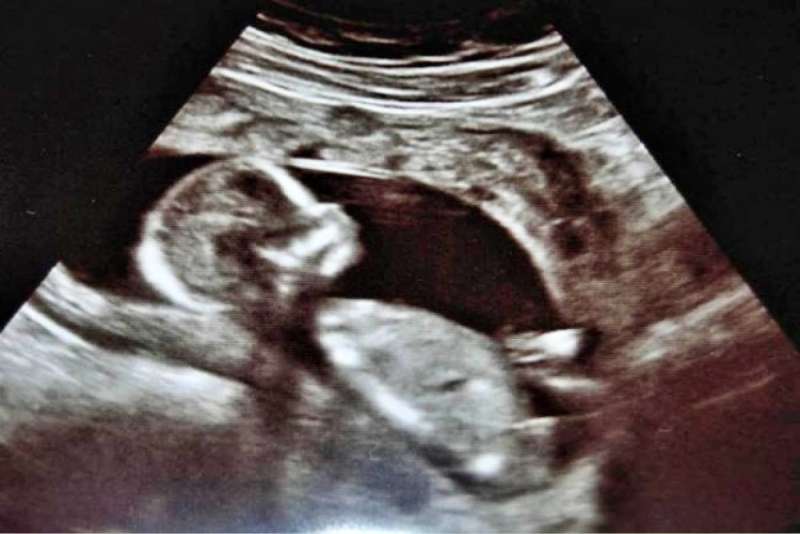

Oaxaca, Oax., a 31 de agosto de 2025.- Las muertes fetales, es decir, aquellas ocurridas durante el embarazo o en el parto, son una problemática de salud que persiste en el estado de Oaxaca, incluso cuando los casos han disminuido en los últimos años.

En su reciente informe de Estadísticas de Defunciones Fetales, el Instituto Nacional de Estadística y Geografía (Inegi), señala que en Oaxaca ocurrieron 312 muertes de este tipo en el año 2024. Esto implica que casi a diario se presentó un caso.

Hasta ahora, las 312 muertes son la cifra más baja de los últimos años, pues en 2023 se reportaron 336 y en el 2022 fueron 439.